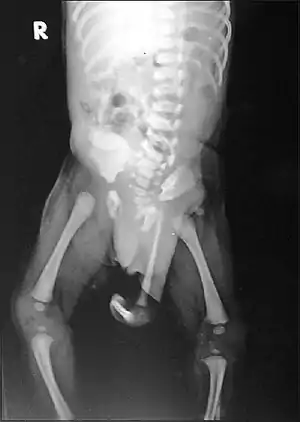

| Radiograph of a human child with polymelia | |

Polymelia is a birth defect in which an affected individual has more than the usual number of limbs. It is a type of dysmelia. In humans and most land-dwelling vertebrates, this means having five or more limbs. The extra limb is most commonly shrunken and/or deformed. The term is from Greek πολυ- "many", μέλεα "limbs".